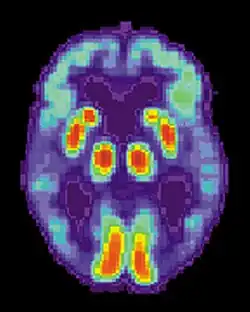

TEP do cérebro de uma pessoa com Alzheimer que revela a perda de funções no lobo temporal.

O diagnóstico da doença de Alzheimer é geralmente baseado na observação comportamental e no historial clínico da pessoa e respetivos familiares. O diagnóstico é apoiado pela presença de características neurológicas e neuropsicológicas e pela exclusão de outras hipóteses.[109][110] A exclusão de outras patologias cerebrais ou outros subtipos de demência pode ser auxiliada por diversas técnicas de imagiologia médica, como a tomografia computadorizada (TAC), ressonância magnética (IRM), tomografia computorizada por emissão de fotão único (SPECT) ou tomografia por emissão de positrões (TEP).[111] Estas técnicas permitem ainda prever a evolução de estádios pródromos (défice cognitivo ligeiro) para a doença de Alzheimer.[112]